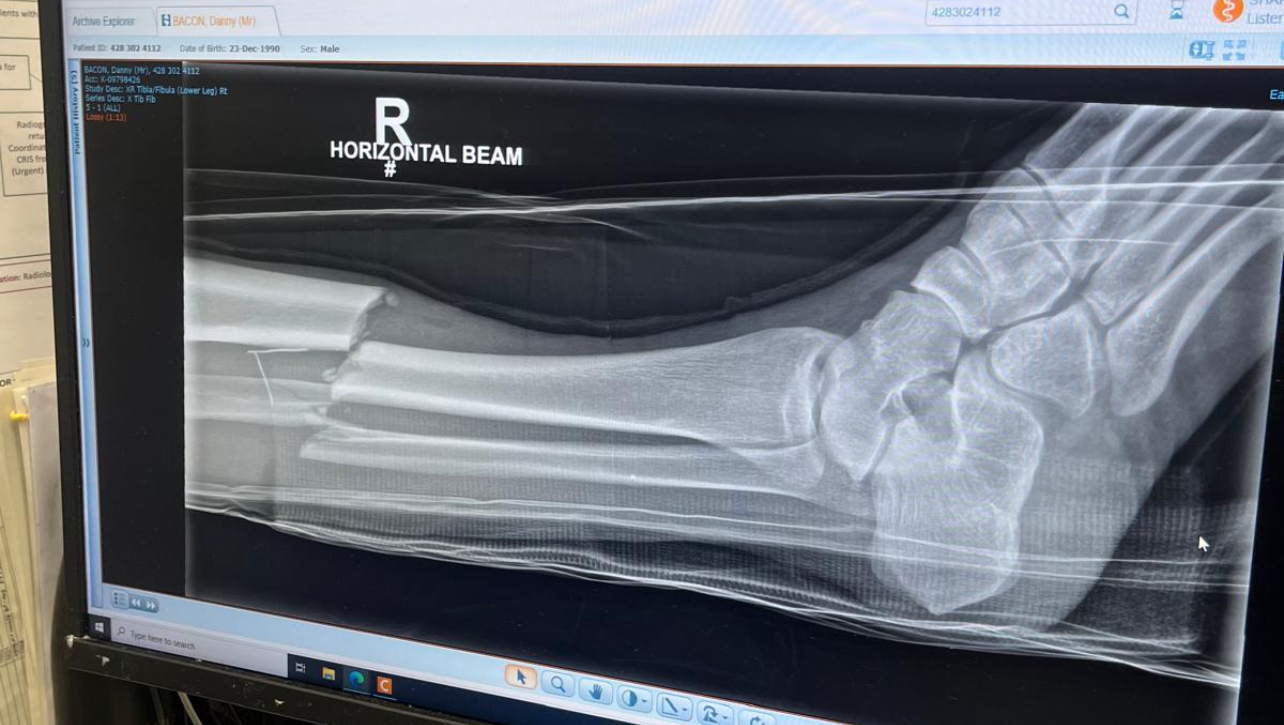

Hi my name is Darryl and I'm looking to raise funds for a close friend of mine Danny who has suffered a nasty double leg break at football. He is self employed and will now be out of work for a lengthy period of time and has a wife and 3 kids to provide for. We would appreciate any donation big or small to help him and is family over the next few months until he is back on his feet and able to work again.